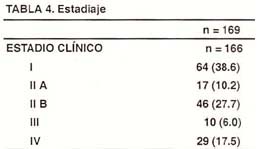

En la Tabla N° 4, se evalúa el estadio clínico de los pacientes con Linfoma Gástrico y se puede apreciar con claridad que la mayoría de los pacientes tienen una enfermedad localizada en abdomen o que pertenecen a los estadios I – II (76.5% de los pacientes), respecto a los pacientes que tienen una enfermedad con compromiso a distancia o estadios III – IV (23.5%), lo que significa que aproximadamente 1 de cada 4 pacientes con Linfoma Gástrico en la presente casuística tiene enfermedad a distancia.